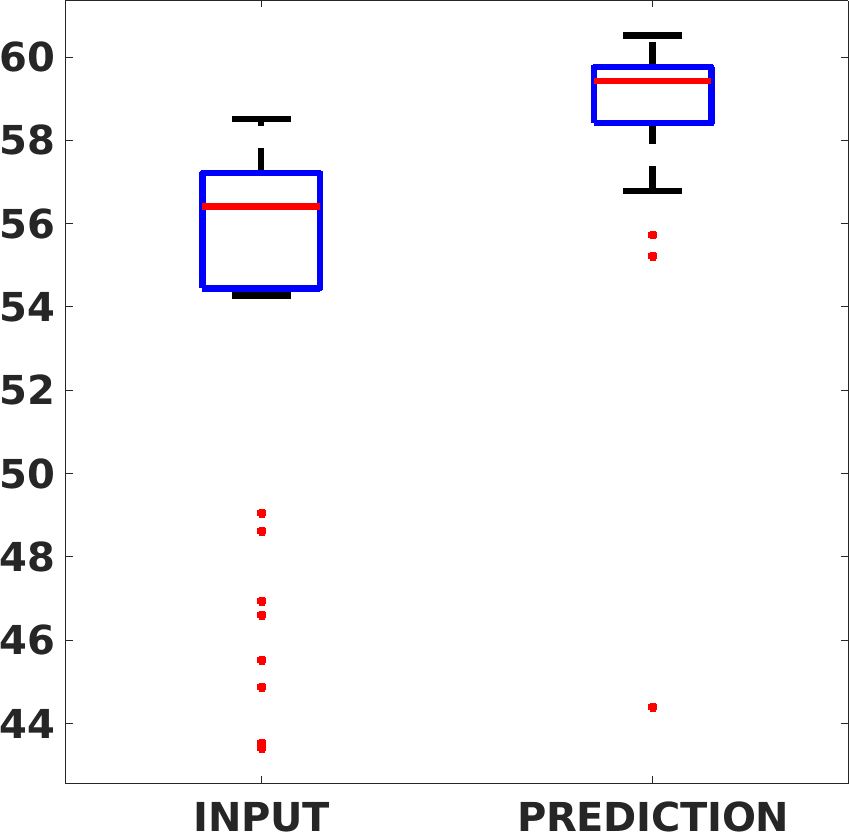

Fig. 7(a-b-c, left) shows the box plot of the statistics of the PSNR on three different anatomical districts, comparing the target images with the prediction and the cubic convolution, respectively. The metrics are computed on a data set of 200 images of the same district and with the same up-sampling factor. We report that the PSNR median value improves of on obstetric 2X raw images, on cardiac 2X raw images, and on abdominal raw 4X images.

Fig. 7(a-b-c, right) shows the histogram of the absolute value of the error with respect to the target image, of the prediction and Cubic convolution results, respectively. The histograms show the number of pixels where the prediction error is lower than 5 (i.e., the first bin of the histogram), which means very similar to the target when visually analysing the images. From the Cubic convolution to the predicted images, this value increases of on obstetric 4X raw images, on cardiac 4X raw images, and on abdominal 4X raw images.

Fig. 17 (left) shows the box plot of the quantitative metrics, comparing the target images with the prediction and the Cubic convolution, respectively. The PSNR metric is computed on a data set of 200 images, belonging to the same district, and with the same up-sampling factor. Analysing the obstetric anatomical district and concerning the corresponding raw images (Fig. 7 (a, left)), the denoising allows the network to significantly improve the results of the up-sampling and the prediction. In particular, comparing the target images with the predicted images, the median PSNR value of obstetric 2X denoised images is 51.8, compared to the median PSNR value of obstetric 2X raw images which is 36.9.